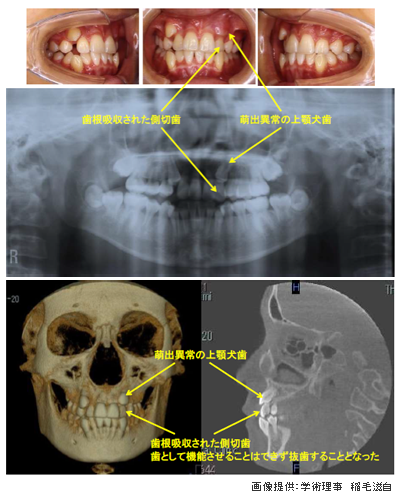

Q3. 犬歯の異所萌出は、なぜ注意が必要なのですか?

A. 隣の前歯の根に影響することがあるからです。

上顎犬歯は、生える位置がズレると、

隣の側切歯(前から2番目の歯)の根を押してしまうことがあります。

その結果、

✔ 歯の根が溶ける(歯根吸収)

✔ 前歯が傾く

といった問題が起こることもあります。

9〜10歳頃に

歯ぐきのふくらみ(バルジ)やレントゲンでの位置確認を行うことが大切です。